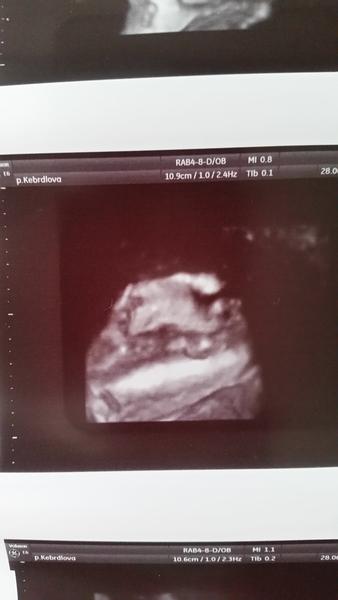

@pulguita tak je to za nami maly si daval rucicku pres oblicej ale neco se povedlo zachytit😉tak chlapecka nam nikdo neodpare je to na tuty😀vyfotila mu i pindika😀jdu pripravovat obed prijede ten pritele kolega a zacnou delat🙂to jsi dobra ze si vybehla a 5km za pul hodiny????tak to bych nedala ale ja az porodim tak chci taky zacit behat😀krasnou stredu

@petrysek181 To je kraaasna fotecka,aspon ze nee vsechny miminka nejsou jako to nase,co se proste neukaze a neukaze😂

@petrysek181 No ten je nádherný😍 Hezky jde vidět. Co na to přítel? Byl na měkko? 🙂

Krásnou středu a zarámuj si tu fotečku, opravdu se povedla🙂